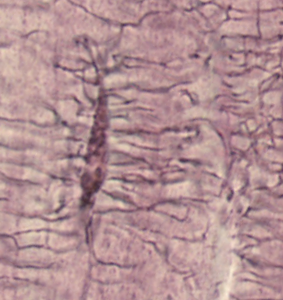

• Tunna kanaler i benmatrix som förbinder lakuner och möjliggör närings-/avfallsutbyte mellan osteocyter.

• Innehåller osteocytutskott; gap junctions mellan celler; radiär riktning genom lameller.